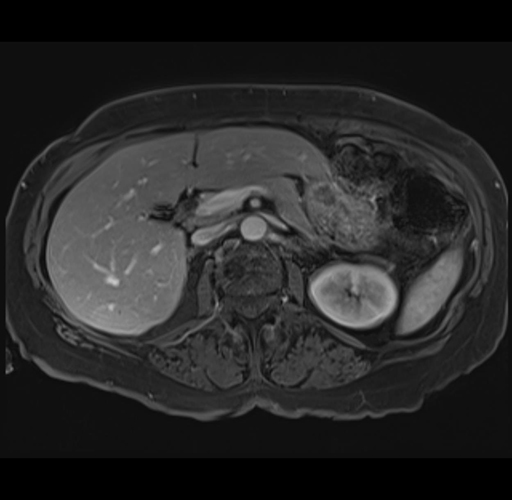

MRI T1